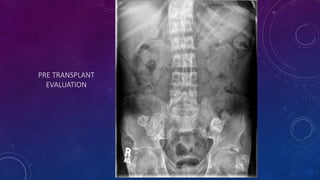

PRE TRANSPLANT

EVALUATION

• Failed kidney transplant

• Seminal vesicle / vas deferens calcification

FAILED BILATERAL RENAL TRANSPLANTS

CALCIFICATION

• #62 Failed kidney transplant Seminal vesicle / vas deferens calcification